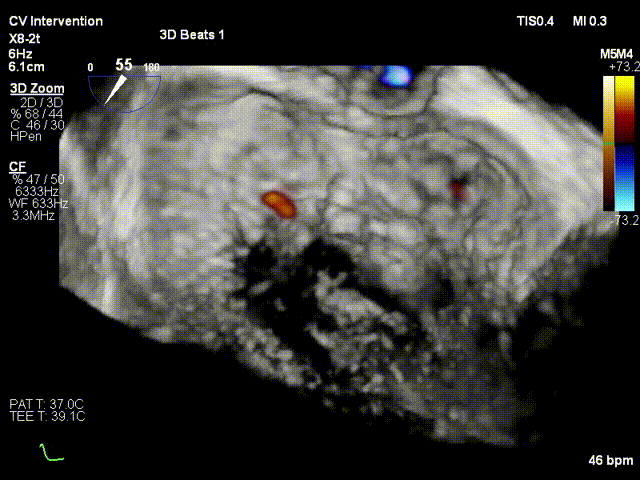

术前3D colour

术后 3D colour view